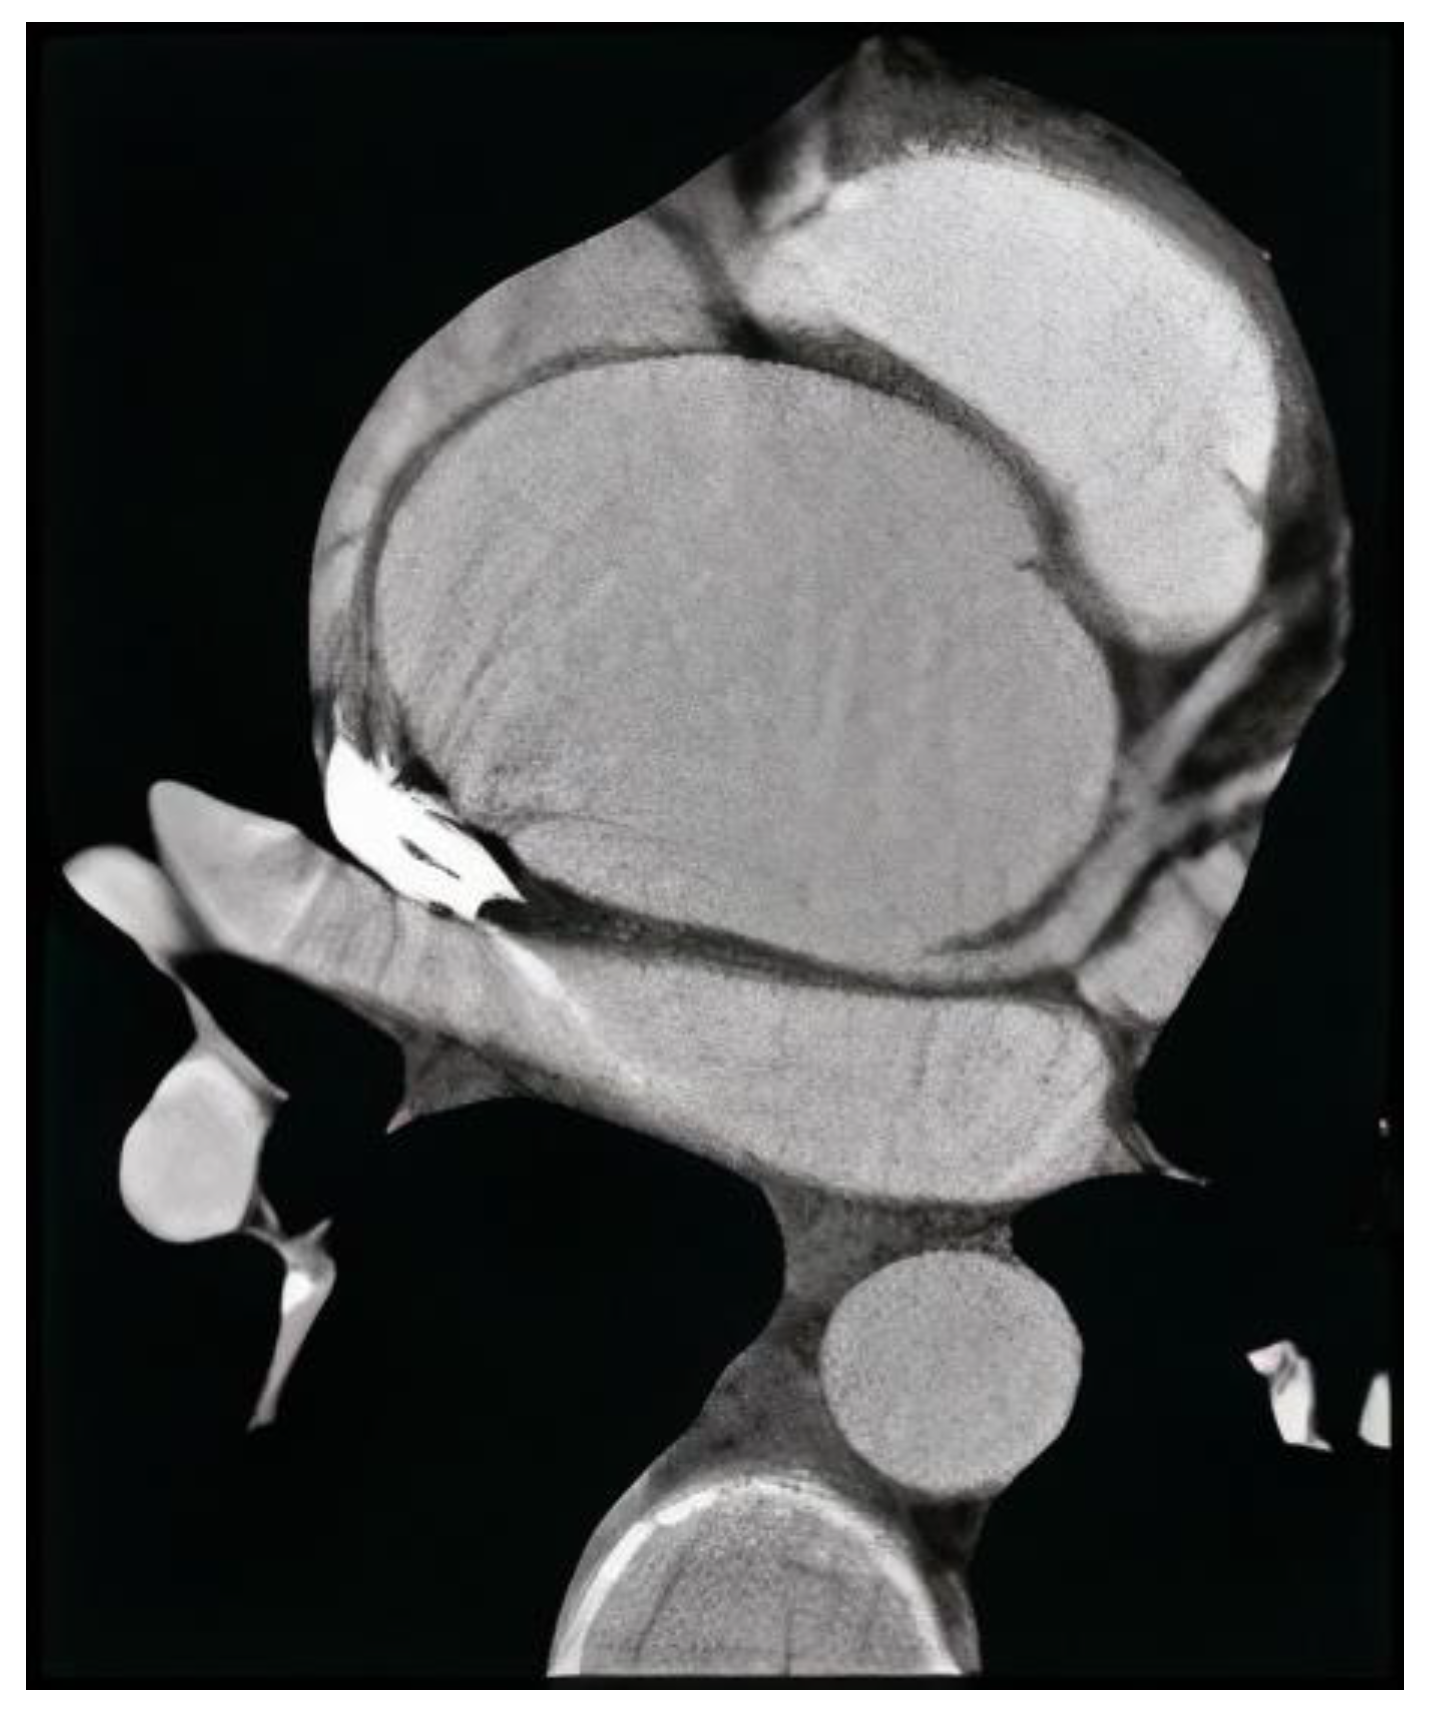

Figure 2.

Angio-computed tomography of thoracic aortic aneurysm with electrocardiographic gating.

ATAA was confirmed by CT scans by the double oblique technique measurement, in which the cross-sectional aorta was determined by averaging the outer-to-outer wall diameters measured at an angle of 60° from one another. Between the sinotubular junction and the proximal take-off of the innominate artery, the greatest part of the aorta was measured. A senior member of the cardiology faculty with expertise in cardiac and thoracic imaging performed the measurements using Syngo.via VB30 imaging software (Siemens Healthineers, Erlangen, Germany). Since the current guideline recommendations for surgical intervention are based on the diameter without indexing, we did not index the aorta diameter by body size [16]. We only took into account aneurysms in the ascending aorta, because the aortic root measurement is prone to motion abnormalities throughout the cardiac cycle, and the scans included both cardiac-gated and non-gated scans.